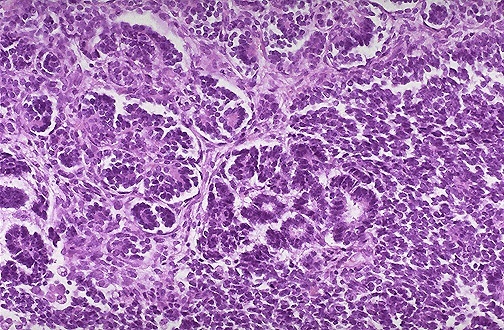

Metanephric adenoma

One of the two main “blue cell” lesions of the kidney (the other being Wilm’s tumor). Thankfully, this one is benign. In fact, it may be effectively a Wilm’s tumor that differentiated/matured.

Usually a 1x diagnosis. It is circumscribed but non-encapsulated tumor of monotonous, small, tightly-packed, dense blue cells with little or no cytoplasm.

The pattern ranges from tiny tubules to serpiginous gland-like structures.